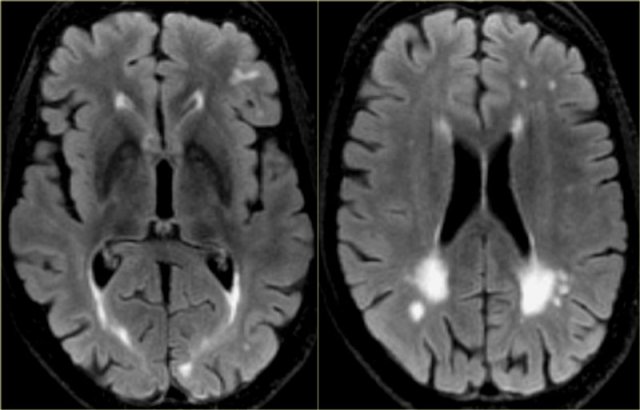

Strategic infarctions

Strategic infarctions are infarctions in areas that are crucial for normal cognitive functioning of the brain.

These areas are summarized in the table.

Strategic infarctions are best seen on transverse FAIR and T2W sequences.

The images show bilateral thalamic infarctions - lesions often associated with cognitive dysfunction.

Study the images of two different patients.

Then continue reading.

The image on the far left shows an infarct in the vascular territory of the Posterior Cerebral Artery (PCA), with involvement of the inferior medial temporal lobe which includes the hippocampus.

This is a strategic infarction, since it is in the dominant hemisphere, it will result in cognitive dysfunction.

The image next to it is a transverse FLAIR image showing another infarct in the PCA-territory, with involvement of the temporo-occipital association area.

This is another example of a strategic infarction that can result in cognitive dysfunction.